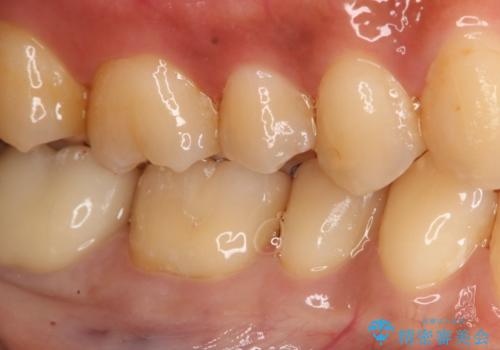

- 過去に他院で治療した部位が材料劣化を起こしていたため、セラミック治療を希望された患者様です。

切削量を考慮し、セラミックインレーを選択しました。

虫歯が深かったので、CRを詰めた上で形態を整えています。